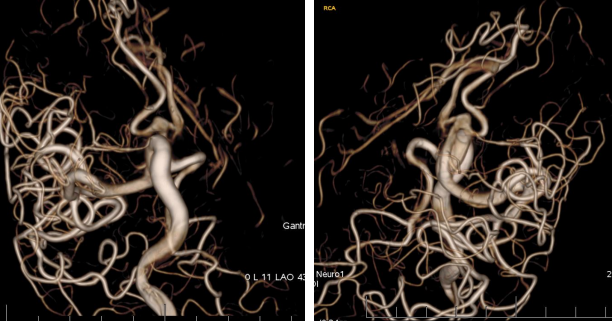

全脑血管造影:右侧大脑中动脉M1分叉处动脉瘤,瘤体3.3 mm*4.1 mm,瘤颈2.7 mm。前交通动脉瘤栓塞完全。

全麻满意后,常规消毒铺巾,采用改良 Seldinger技术穿刺右侧股动脉成功,置入6F动脉鞘。黑泥鳅导丝带领5F单弯导管行脑动脉造影,右侧颈内动脉造影见:右侧大脑中动脉M1分叉处动脉瘤,瘤体3.3 mm*4.1 mm,瘤颈2.7 mm。前交通动脉瘤栓塞完全。

患者在全麻下、多参数监护仪监测下行前交通动脉瘤经右侧颈内动脉支架辅助下栓塞术。全麻后,常规消毒销巾,采用改良seldinger技术穿刺右侧股动脉或功,置入6F动脉鞘。黑泥鳅导丝及多功能导管带领6F MPD导管达到右侧颈内动脉岩段,行造影见∶前交通动脉瘤,瘤体3.5 mm*5.1 mm。在路图引导下,徵导丝(Synchro 0.014 in*200 cm)带领弹支架微导管(SL-10)到右侧大脑前动脉A2段,退出微导丝。微导丝(Synchro 0.014 in*200 cm)带领弹簧圈微导管(eV3 Echelon-10)到达前交通动脉瘤体内,退出微导丝。经弹簧圈微导管填入首枚弹簧圈(Codman COMPLEX XTRASOFT3 mm*6 cm)成篮良好,在路图引导下在支架管内输送支架(Neuroform Atlas 3.0 mm*21 mm)并释放完全覆盖动脉瘤颈,造影可见支架打开良好解脱首枚弹备圈,沿弹簧圈导管继续填入弹簧圈(可见护理记录单)间断造影确保双侧大脑前动脉血流通畅。右侧颈内动脉造影确认∶前交通动脉瘤填塞致密,双侧大应前动脉血流通畅。手术结束。右侧股动脉鞘处用血管封堵器(Coxrds Exoseal 6F)封堵,并压迫器持续压迫。木后患者清醒。

颅内动脉分叉处宽颈动脉瘤一直是介入治疗的一个难点,存在支架到位困难、介入栓塞术后复发率高的特点。大脑中动脉分叉部动脉瘤与前交通动脉瘤临床使用Neuroform Atlas新型支架,有望进一步提高支架到位与栓塞成功的比率。

Neuroform Atlas支架系统是Neroform支架的新一代产品,其改进后的设计可以使支架经更细的微导管输送(Atlas可以通过0.0165 inch内径的微导管输送,而以前的支架产品一般只能通过0.027 inch内径的较粗微导管输送)。较前代Neuroform支架相比,Atlas支架在操作上易输送,通过性强,易定位、释放,释放时张力小,无明显上下移位,贴壁性好,Atlas支架具有更佳的“脚手架”作用。